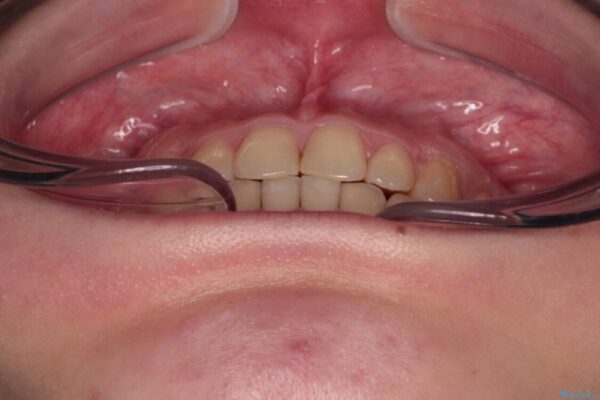

根管治療を行ったままの奥歯と、矯正治療の後戻りを気にして来院された患者様です。

根管治療された歯に症状はなく、オールセラミッククラウンにて補綴治療を行うこととしました。

矯正治療の後戻りは軽微であったため、インビザラインの簡易パッケージであるインビザライン・ライトを用いて歯列を整えることとしました。

クラウンはよりよい咬み合わせで装着したいため、インビザラインを1セット使用して概ね歯列を整えた時点で補綴治療を行い、その後仕上げの矯正治療を行いました。

治療前

• 治療途中の奥歯と矯正治療の後戻り インビザライン・ライトによる矯正治療 治療前画像